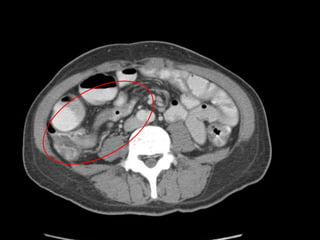

Pt underwent CT scan of the abdomen

• Work up :

 CT abdomen and pelvis with IV contrast

FINDINGS :

Multiple mesenteric lymphadenopathies

, largest one measuring 1.7cm.

Mild hepatomegaly.

Jejunization of the ileum